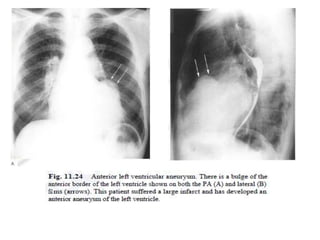

Left ventricular aneurysm

• large infarcted segment and sustains full-

thickness ischemia- may develop into a left

ventricular aneurysm (over a few weeks).

• most commonly at the cardiac apex in

association with an anterior infarct , but it can

also occur in the posterior position.

• The chest radiograph: localised bulge on the

left heart border but if the aneurysm is not

well demarcated or if it lies in a less prominent

position it may not be identified on the plain

film.